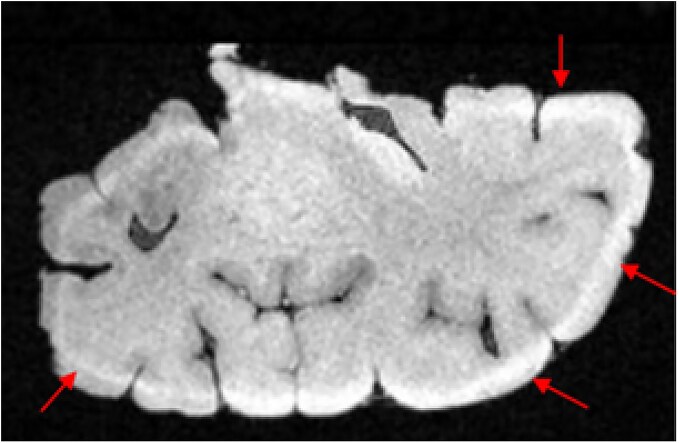

Ex vivo magnetic resonance imaging (MRI) has revolutionized psychoradiological research by enabling detailed structural and pathological assessments of the brain in conditions ranging from psychiatric disorders to neurodegenerative diseases. By providing high-resolution images of postmortem brain tissue, ex vivo MRI overcomes several limitations inherent in in vivo imaging, offering unparalleled insights into the underlying pathophysiology of mental disorders. This review critically summarizes the state-of-the-art ex vivo MRI methodologies for neuroanatomical mapping and pathological characterization in psychoradiology, while also establishing standardized specimen processing protocols. Furthermore, we explore the prospects of application in ex vivo MRI in schizophrenia, major depressive disorder and bipolar disorder, highlighting its role in understanding neuroanatomical alterations, disease progression, and the validation of in vivo neuroimaging biomarkers.